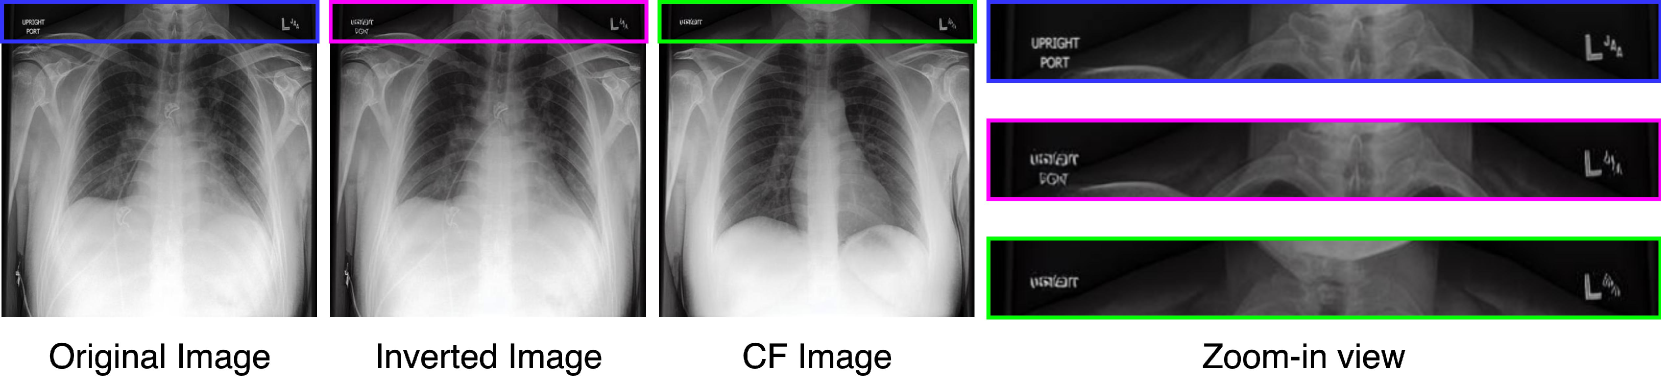

Appendix I Limitations of PRISM

Although our method is capable of synthesizing high-resolution images (512×512512512512\times 512512 × 512), it faces difficulties in reproducing the small text written in the corner of radiographs (Fig 14) in both the inverted and CF images. This inability of Stable Diffusion to resolve fine text is a known phenomena and is also seen in natural images [Mokady et al.(2023)Mokady, Hertz, Aberman, Pritch, and Cohen-Or].

Refer to caption

Figure 14: Text at the corner of the image remains unresolved in the inverted and edited images.